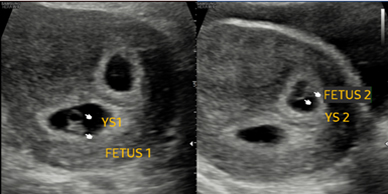

Skanda Advanced Ultrasound Scan Centre starts right from the onset of pregnancy. Our Fetal Medicine experts are concerned with the health of the fetus at every stage – monitoring growth & development; predicting, detecting & managing any complications; and treating congenital disorders & anomalies in the womb itself.